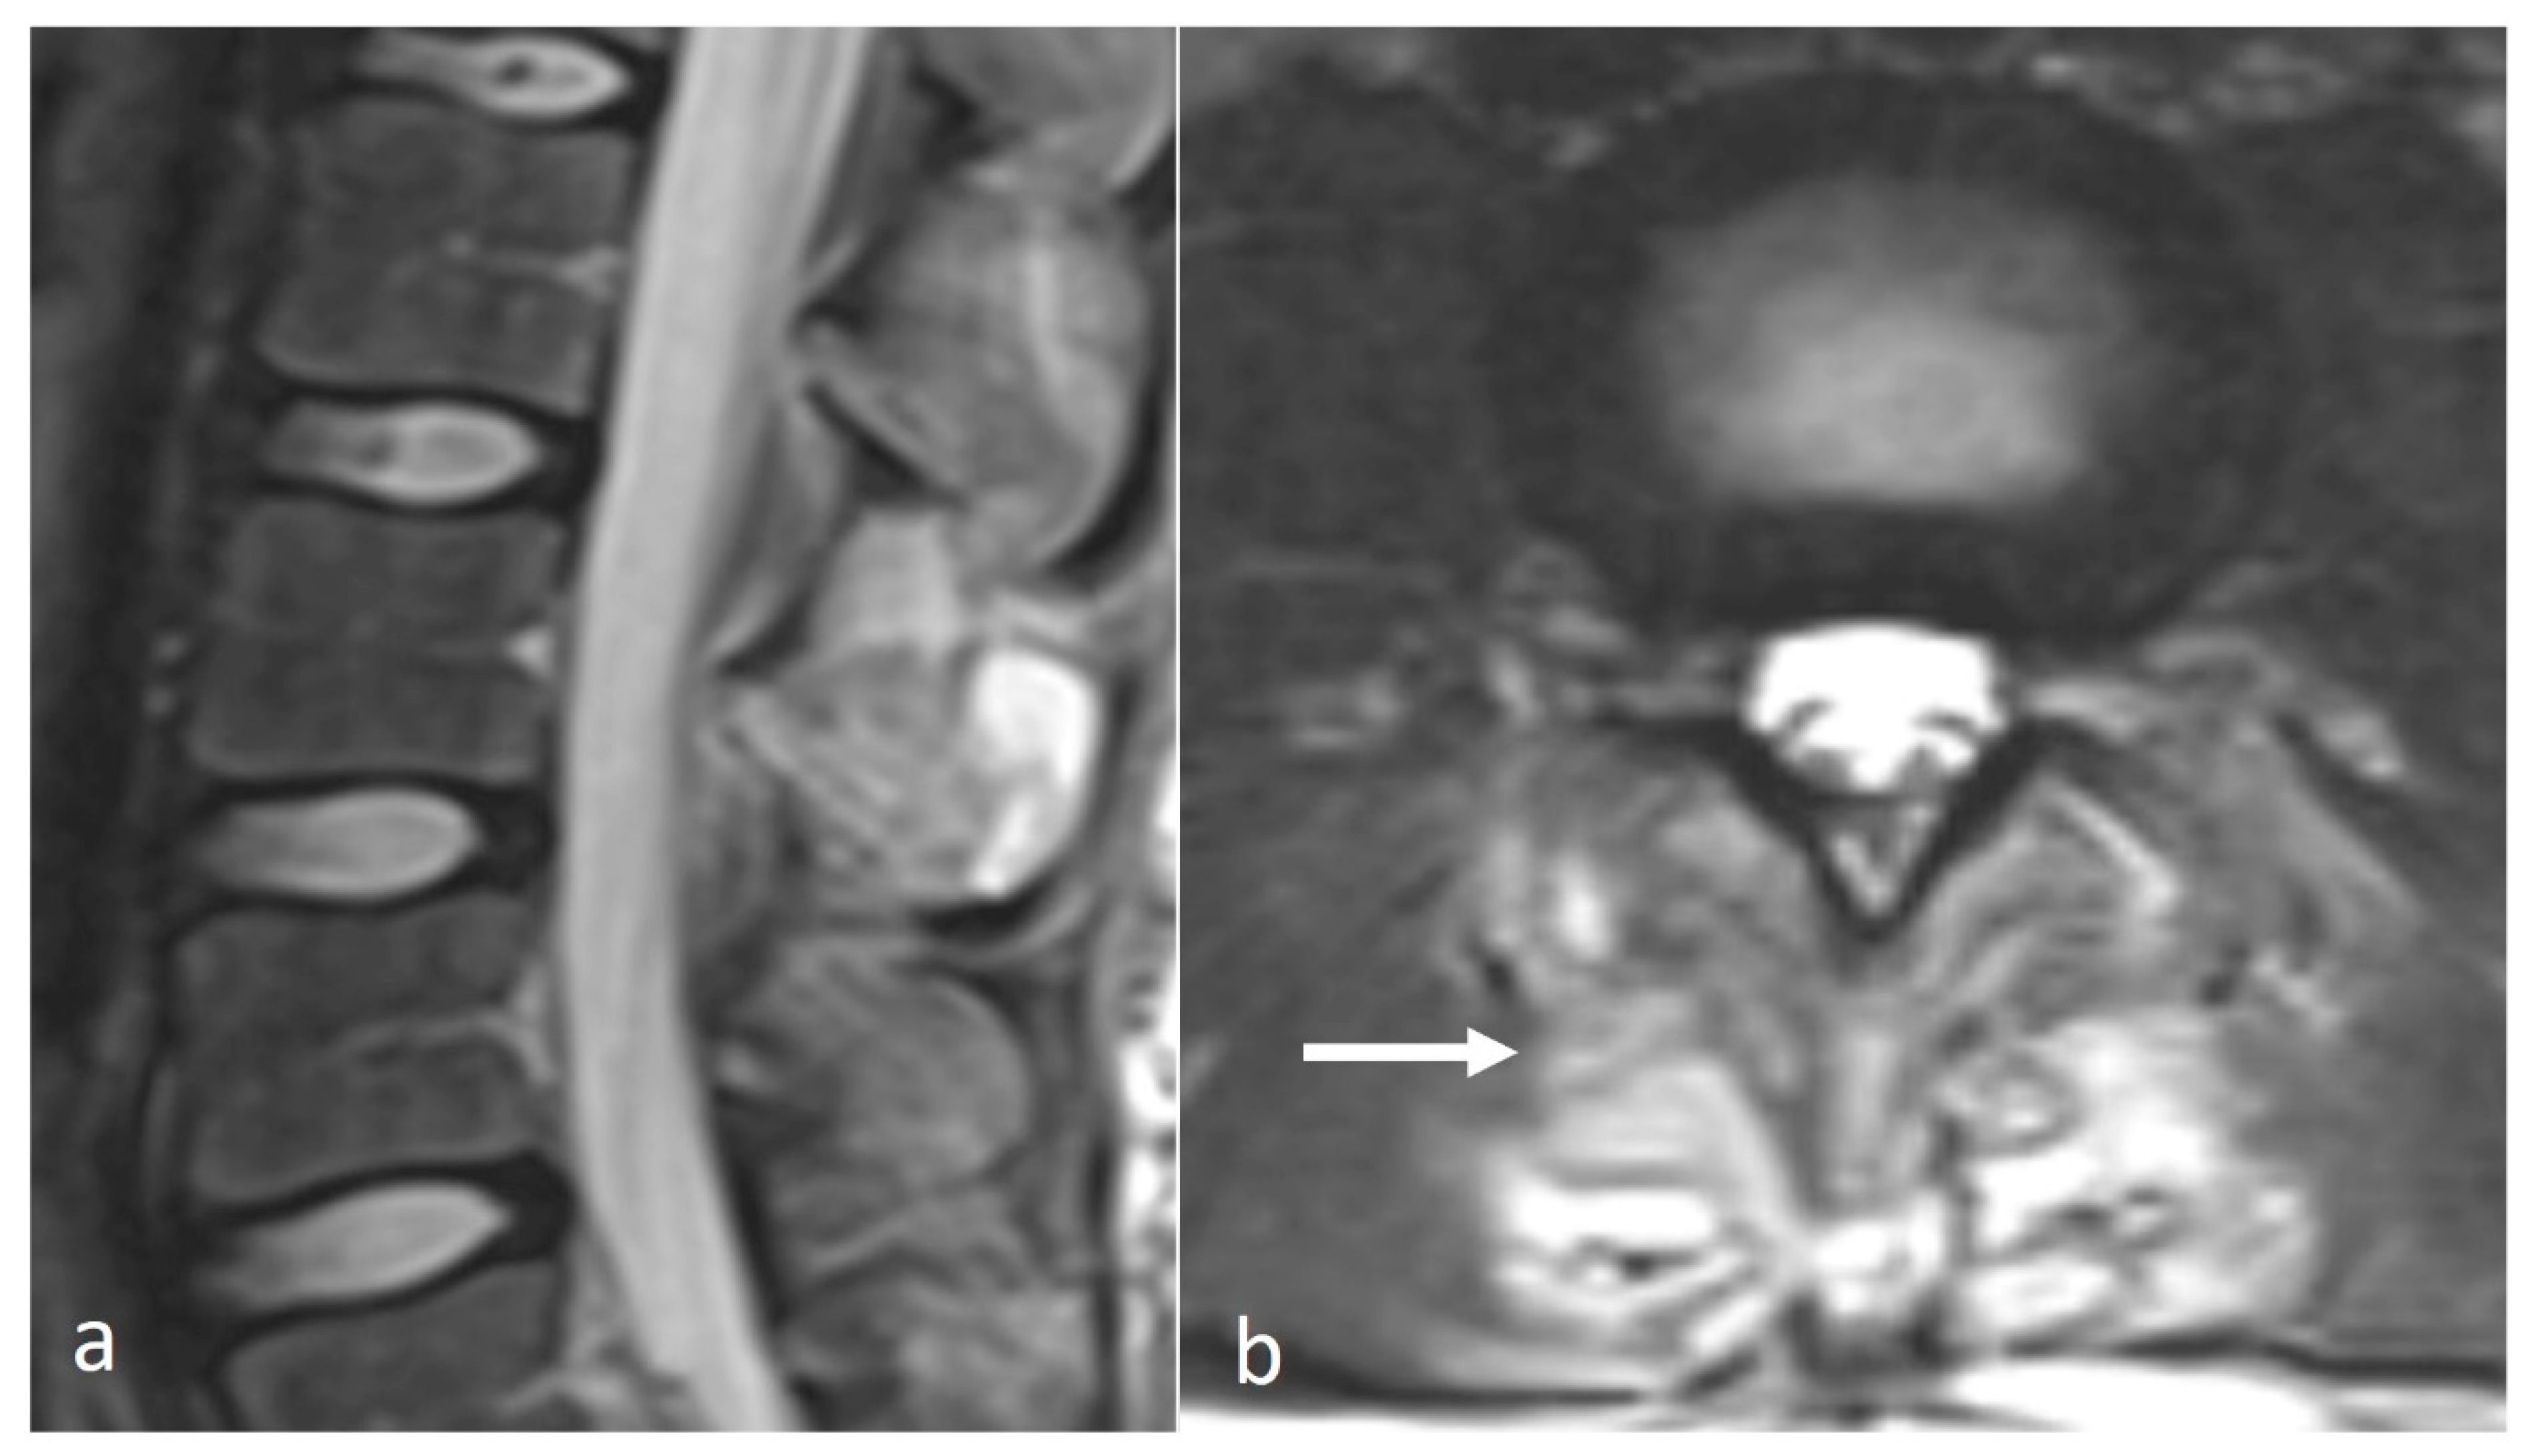

Osteoid osteomas (OOs) account for 10–14% of primary vertebral tumours. The majority are seen in the lumbar spine, followed by the cervical and thoracic spine. Given their predilection for the posterior elements, involvement of the spinous process is not uncommon [15,16]. MRI is sensitive and may show marrow oedema; however, the oedema can obscure the nidus, which can be a potential pitfall. On MRI, the nidus when seen is of low to intermediate T1 signal, ofvariable T2 signal with areas of signal void due to mineralisation (Figure 2a). The nidus may also show variable enhancement on post-contrast imaging [15,16]. Lesions may be occult on a radiograph. The presence of sclerotic reactive bone surrounding a lucent nidus is a typical feature on CT, although the latter may not always be present (Figure 2b). A central sclerotic dot may also be present. The nidus is typically <1.5 to 2 cm in diameter.

Figure 2.

Sagittal STIR (a) and CT (b) images demonstrating a thoracic spinous process osteoid osteoma (white arrows). Note the presence of reactive marrow oedema on the STIR sequence. The sclerotic reactive bone is well delineated on CT, although the lucent nidus may not always be present as in this case.